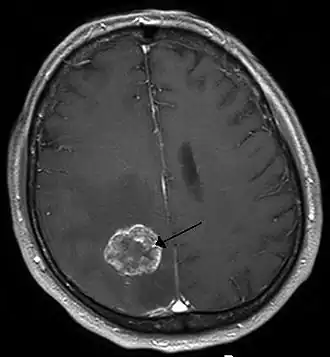

Опухоль головного мозга, визуализированная с помощью МРТ - 26 мая 1803 г. профессоор Е. О. Мухин провёл в Москве в Голицынской больнице первую в истории России успешную нейрохирургическую операцию[2]. В 1807—1808 гг. в Санкт-Петербурге было издано оригинальное «Руководство к преподаванию хирургии» И. Ф. Буша. В разделе «О повреждениях черепа» автор рекомендовал производить рассечение раны мягких тканей c удалением мелких свободно лежащих костных фрагментов, инородных тел и сгустков крови; крупные костные фрагменты рекомендовалось трепанировать, обнаруженным внутричерепным кровоизлияниям «давать выход». Выполнение собственно трепанации, то есть расширения имевшегося костного дефекта, рекомендовалось только при наличии симптомов сдавления мозга, к каковым относились головная боль, судороги, воспаление и лихорадка и при больших кровоизлияниях — сужение зрачка, замедление пульса и нарушения дыхания.